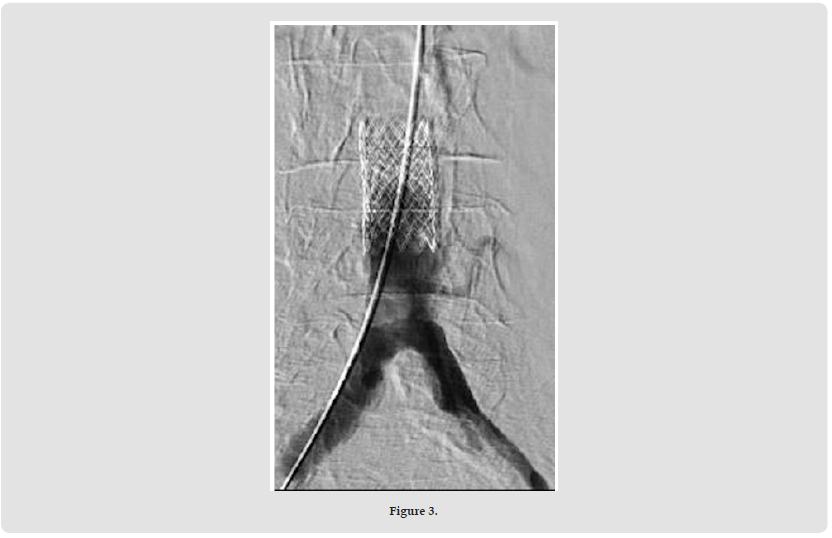

On the right side, the 18x38 mm BeGraft® Aortic Stent Graft (Bentley) was positioned halfway between the inferior mesenteric artery and the bifurcation, as planned (Figures 2 & 3). From both sides, a 10x37 mm BeGraft® Peripheral Stent Graft (Bentley) was deployed without predilatation into the iliac artery, positioned 10 mm up the aorta. After opening with a simultaneous kissing technique, angiography showed good results (Figure 4) and then the left side was stented with an 8x37 mm BeGraft® Peripheral Stent Graft (Bentley) with 10 mm overlap. The overlap was re-expanded with the 10 mm BeGraft® peripheral balloon. On control angiography, the inferior mesenteric artery and both internal iliac arteries remained open (the left side was also patent despite the preliminary CTA image) (Figure 5).